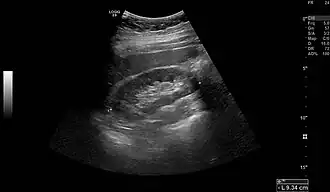

Normal adult right kidney as seen on abdominal ultrasound with a pole to pole measurement of 9.34 cm -

Renal ultrasonography is essential in the diagnosis and management of kidney-related diseases.[49] Other modalities, such as CT and MRI, should always be considered as supplementary imaging modalities in the assessment of renal disease.[49]